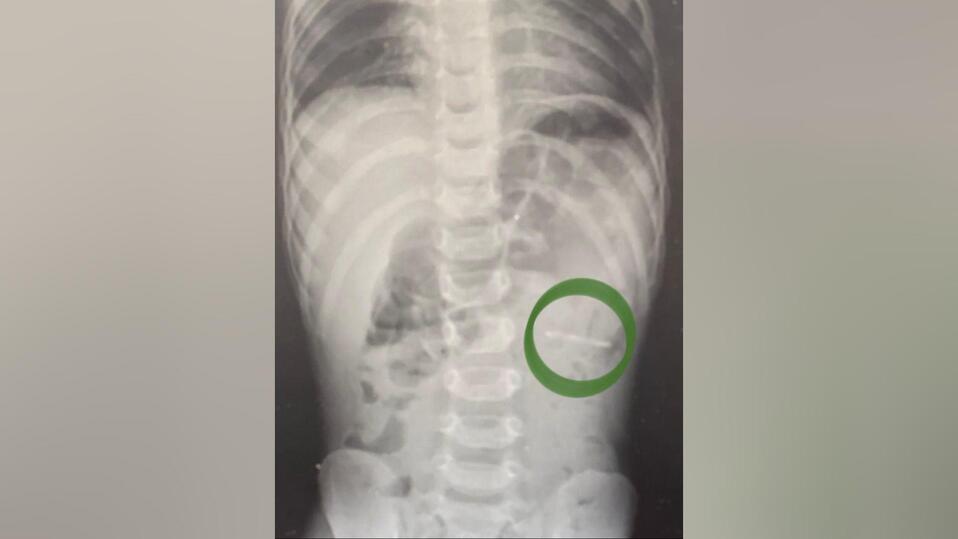

Ключ от металлической банки умудрился проглотить полуторагодовалый малыш, госпитализированный в больницу подмосковного Раменского.

Как сообщили «МК» в Минздраве Московской области, обнаружить изделие в брюшной полости удалось благодаря рентгену. К счастью, слизистые оболочки не были повреждены. С помощью эндоскопа ключ извлекли, мальчик отделался легким испугом.